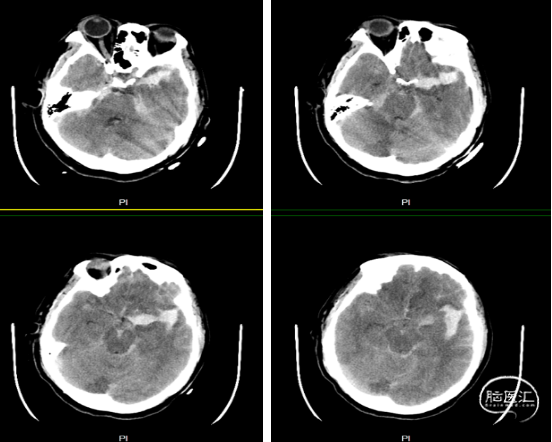

入院头颅ct显示双侧蛛网膜下腔,纵裂,基底池脑室广泛出血

图1. 头颅ct示广泛蛛网膜下腔出血,左侧侧裂为主. 术前dsa(图2)结果